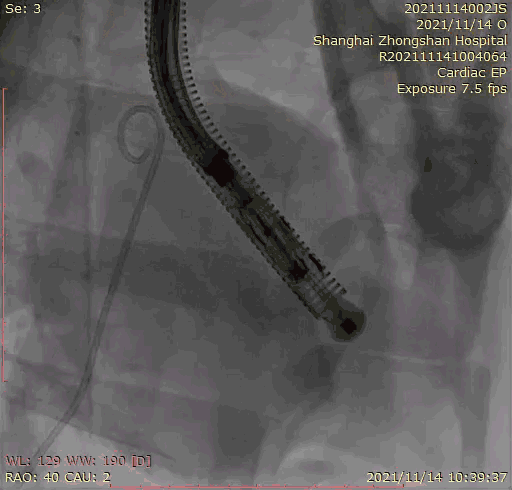

2021年11月14日星期日,復(fù)旦大學(xué)附屬中山醫(yī)院(以下簡稱中山醫(yī)院)葛均波院士團(tuán)隊(duì)成功應(yīng)用經(jīng)血管介入三尖瓣置換產(chǎn)品Lux-Valve Plus完成臨床前研究,并獲得圓滿成功!此次研究的成功預(yù)示經(jīng)血管三尖瓣產(chǎn)品Lux-Valve Plus已完成臨床前準(zhǔn)備,即將開啟后期的正式臨床研究!

上海中山醫(yī)院葛均波院士、錢菊英院長、周達(dá)新教授、潘文志教授、潘翠珍教授、李偉教授共同完成此次臨床前研究。術(shù)后葛均波院士對Lux-Valve Plus的器械操作性能給予了高度評價(jià),DSA和超聲影像也顯示出在本次研究中Lux-Valve Plus的安全性和有效性俱佳。

本次臨床前研究經(jīng)右側(cè)頸靜脈置入LuX-Valve Plus輸送系統(tǒng)可調(diào)彎鞘管,在DSA及超聲引導(dǎo)下將人工三尖瓣瓣膜植入到原有三尖瓣位置,利用獨(dú)特的錨定技術(shù)將人工瓣膜支架可靠固定在預(yù)定的位置。